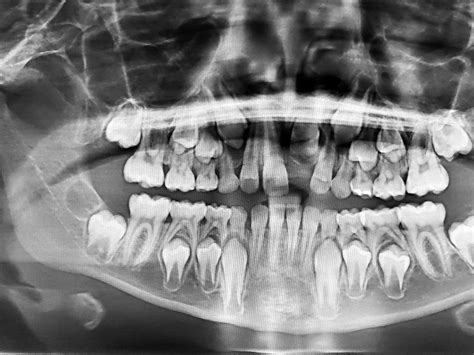

Radiografía dental en niños para diagnóstico y tratamiento.

Las radiografías dentales en niños son una de las mejores herramientas de prevención y diagnóstico disponibles. Se utilizan para obtener una imagen completa de las coronas y raíces dentales superiores e inferiores, permitiendo a los odontólogos detectar problemas que no son visibles a simple vista. Las radiografías son esenciales para prevenir, diagnosticar y tratar numerosas alteraciones relacionadas con el desarrollo bucal en los niños.

Cuando se planifica un tratamiento de ortodoncia, las radiografías de boca se convierten en un aliado indispensable. Permiten evaluar la cantidad de espacio disponible para los dientes en erupción, determinar si el hueso ha finalizado su fase de crecimiento y detectar dientes impactados o la posición de los dientes por debajo de la encía y en el hueso.